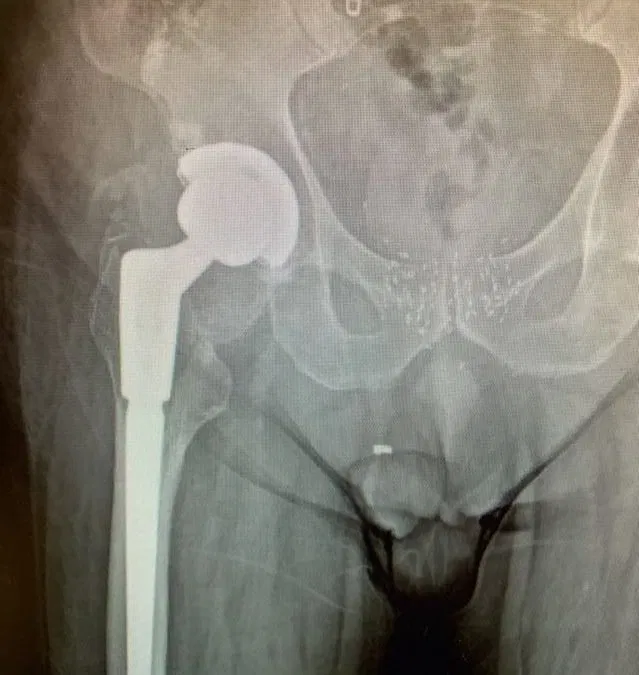

Case Study of Loosening of Left Total Hip Arthroplasty

Case Study of Loosening of Left Total Hip Arthroplasty Patient is a 70 year old male who came in with severe left hip pain after having a left Total Hip Arthroplasty (THA) done several years ago. On initial visit with us, X-Rays showed findings of periprostheticlucency/osteolysis of the femoral stem and mild thickening of...